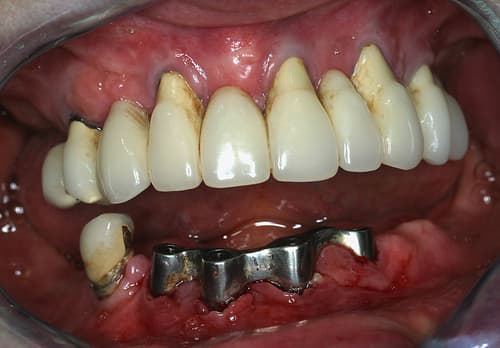

Pré-opératoire